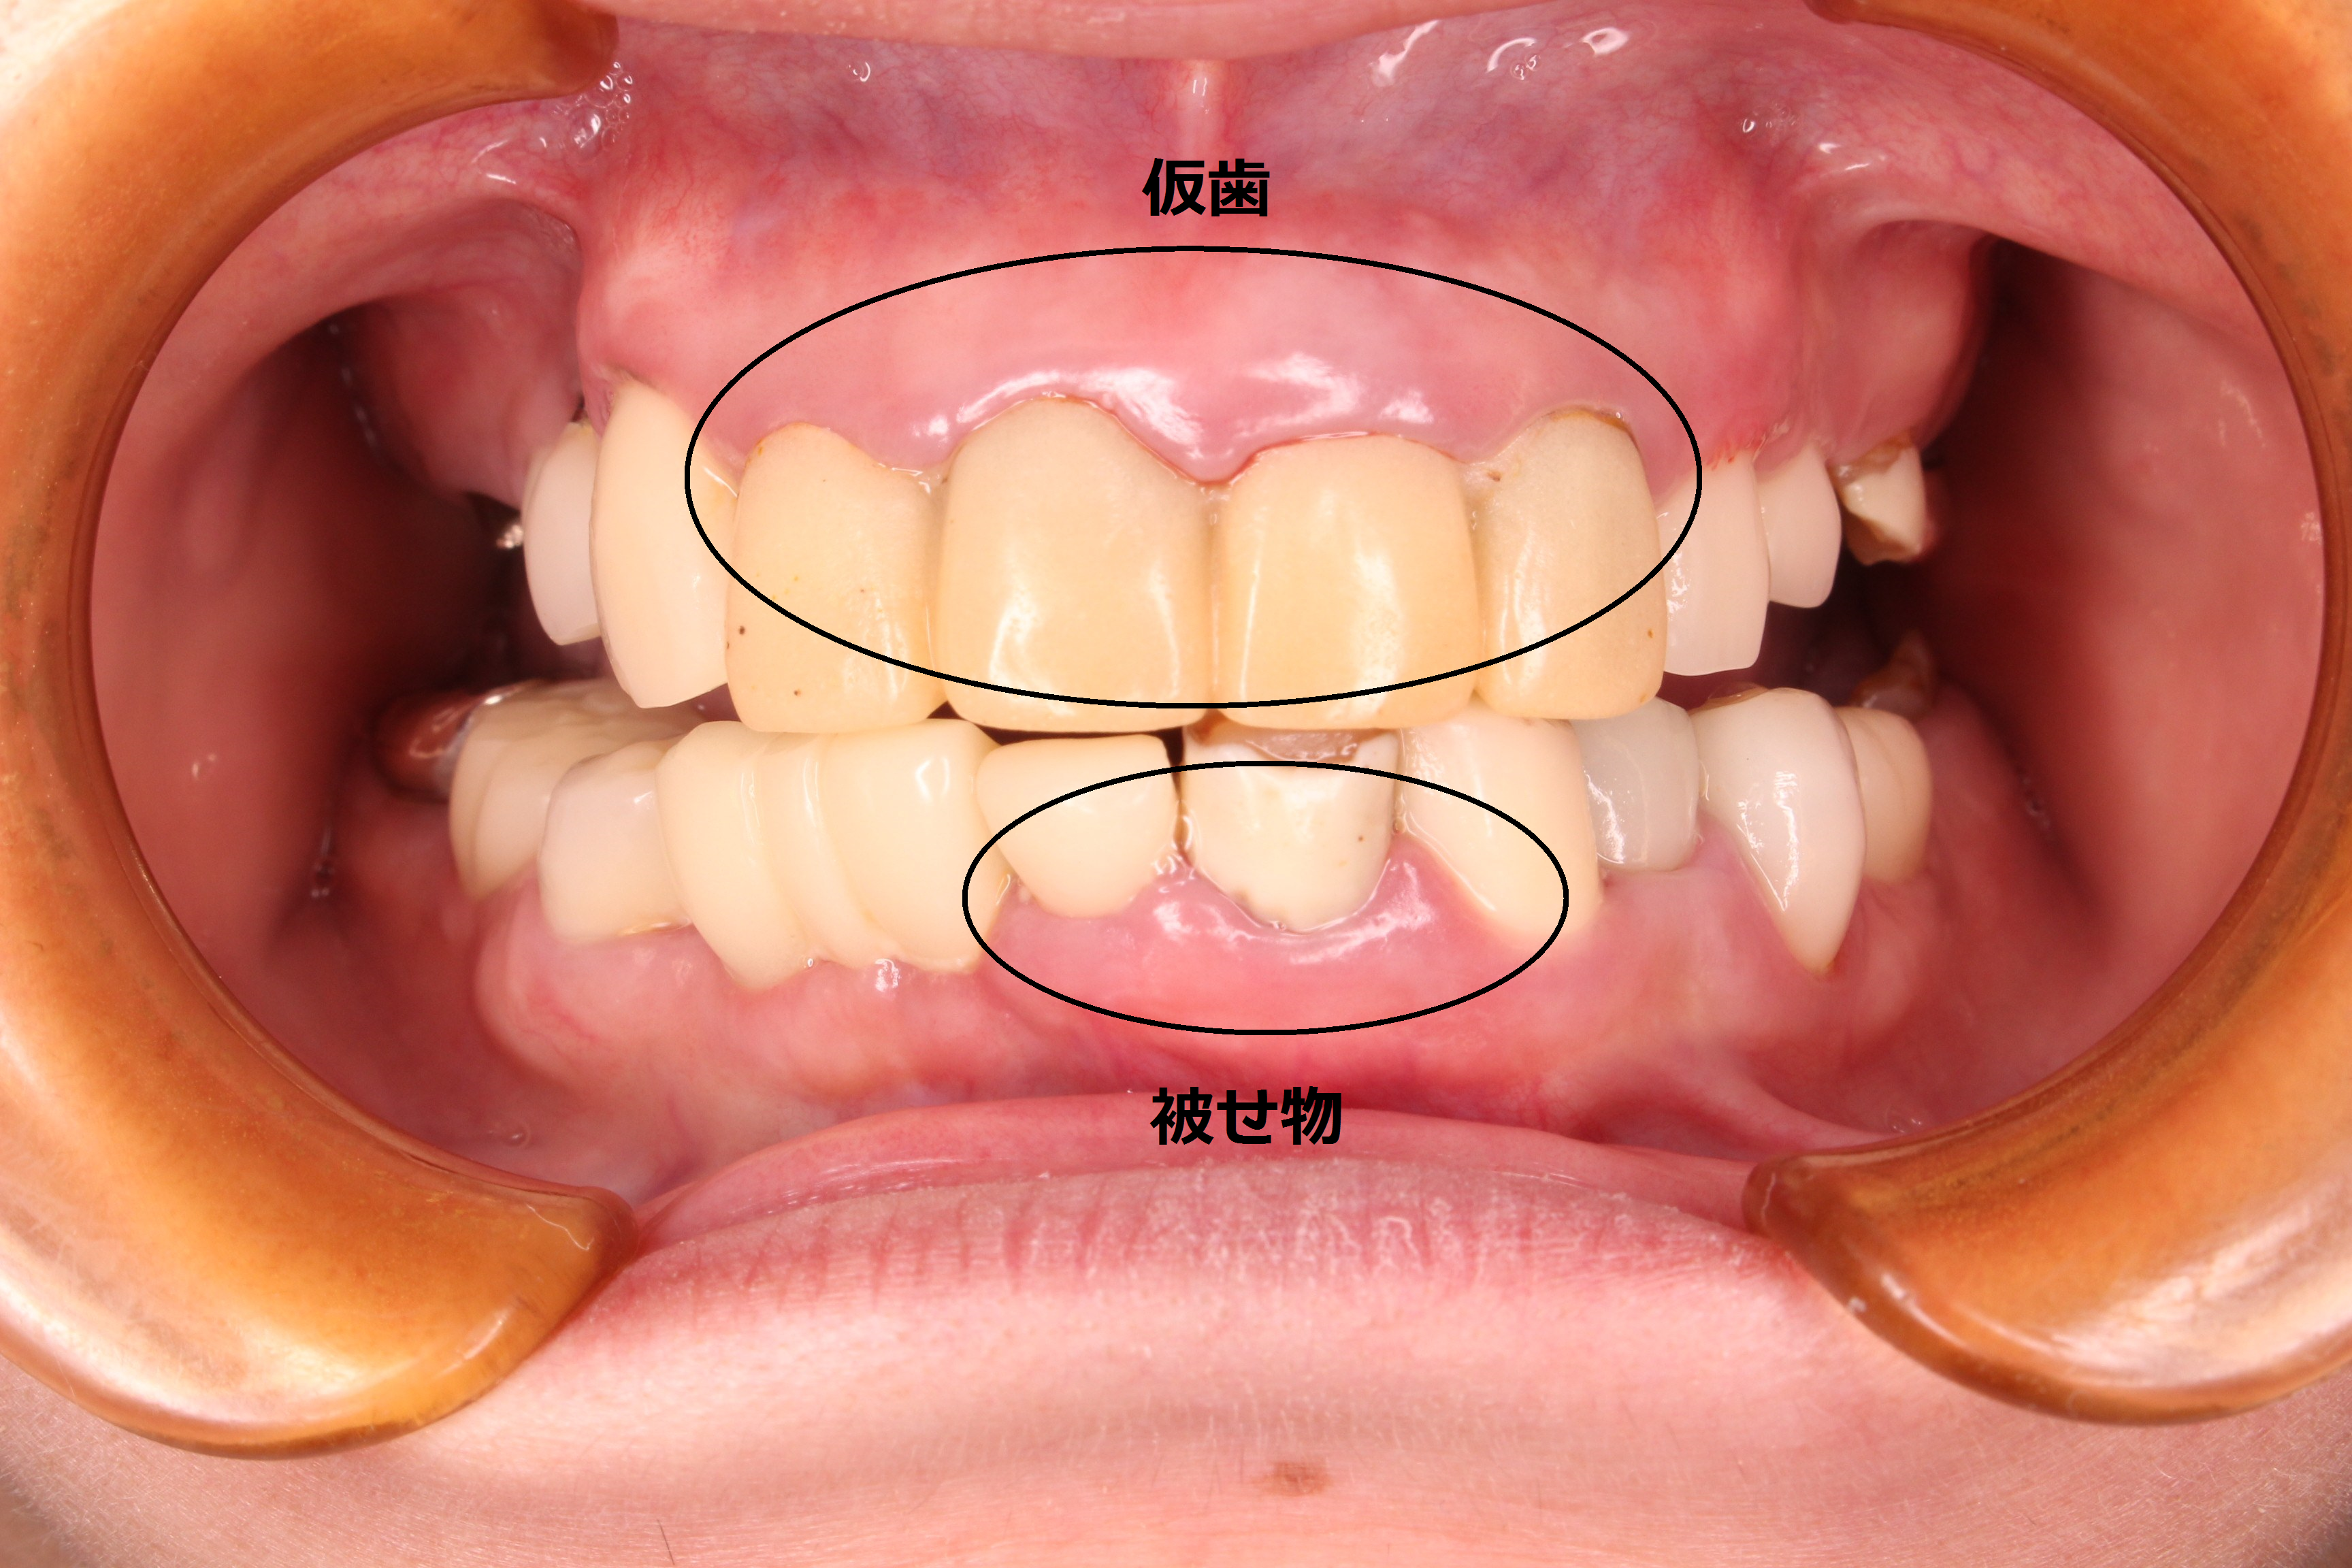

初診時 口腔内写真

全体的に炎症(発赤、腫脹、出血、排膿等)が広がっており、数年前に他院で入れたインプラント部の周辺歯肉も腫れ上がり、排膿していました。

ほぼ全ての歯に被せ物等の治療がしてあることからも、歯の治療で苦労してきたことが伺えます。